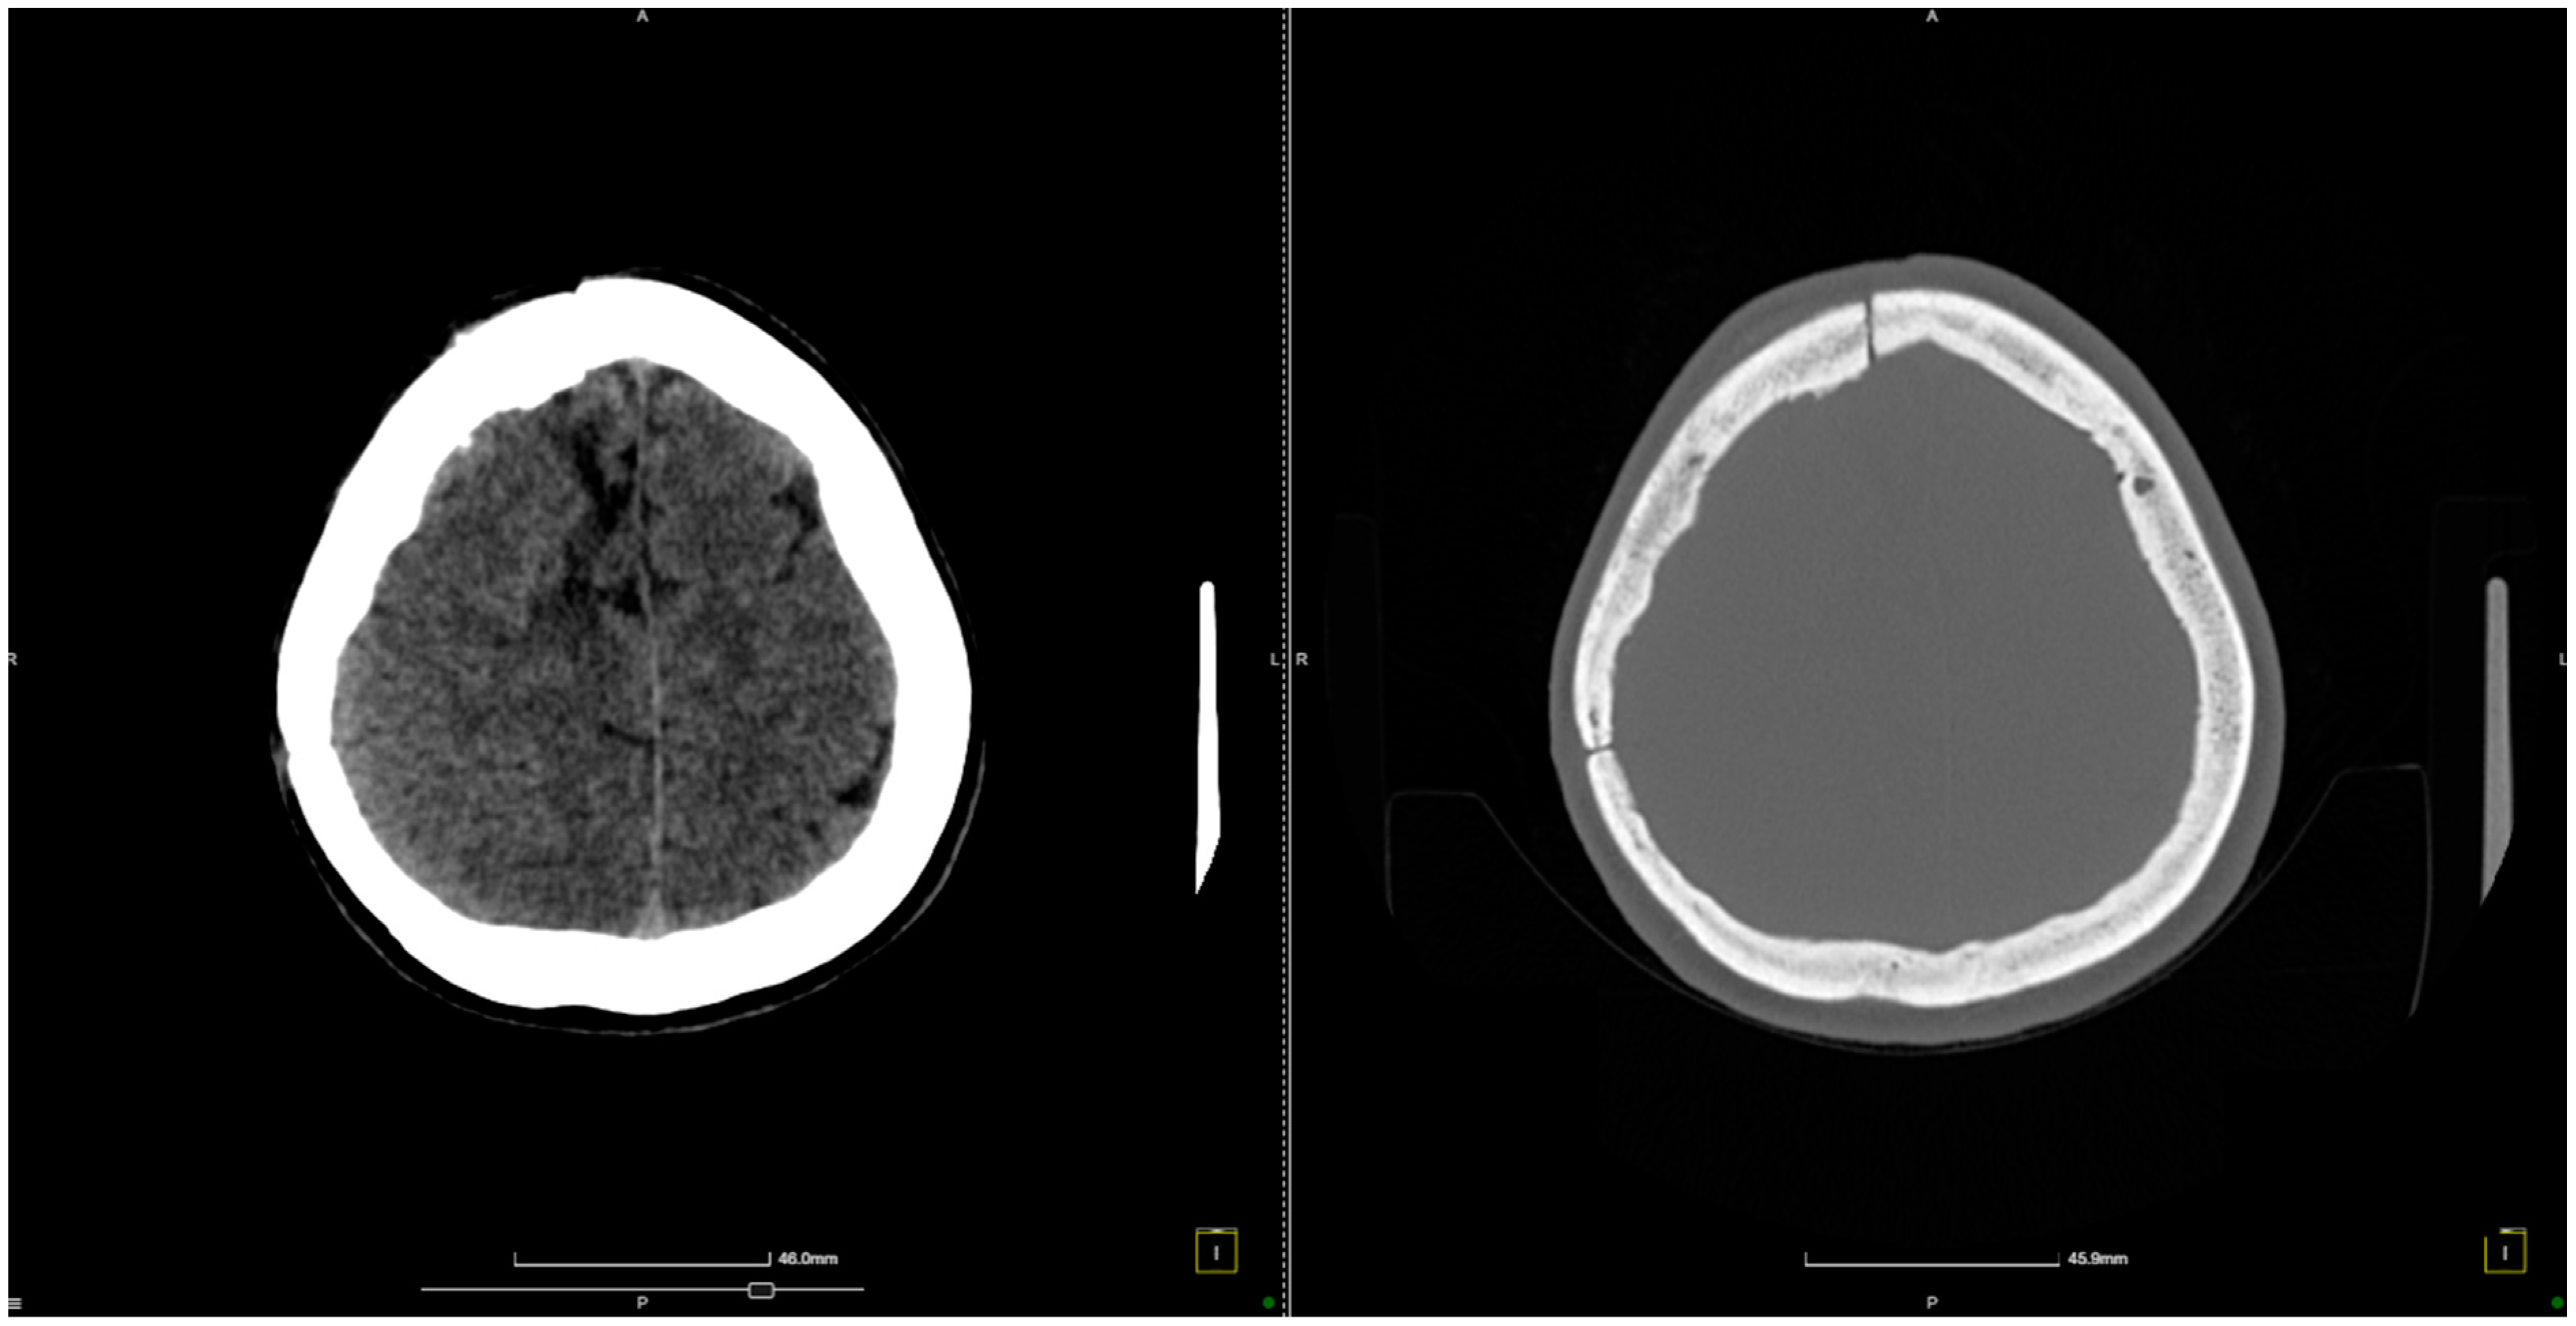

2. Case Presentation